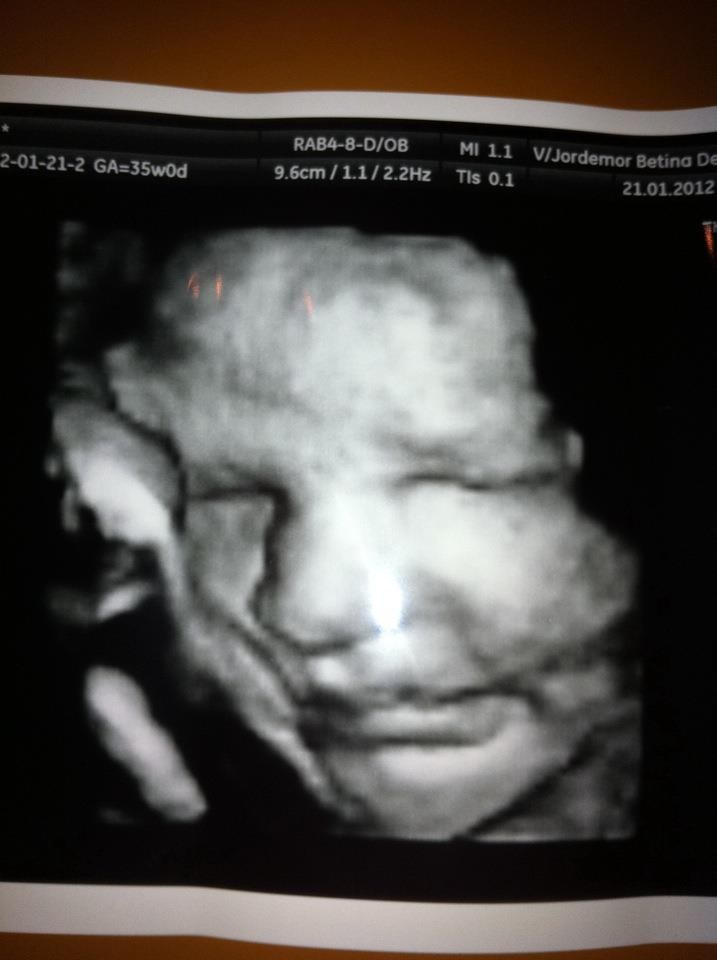

2: lillebror Sylvester

... Det tredje billed er for at sammenligne med vores den mindste, syntes de ligner hinanden meget godt